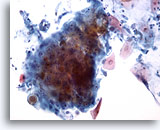

Figure 83

Bronchial wash

A pearl of keratinized cells from a case of squamous cell carcinoma.

60x

Bronchial wash

A pearl of keratinized cells from a case of squamous cell carcinoma.

60x